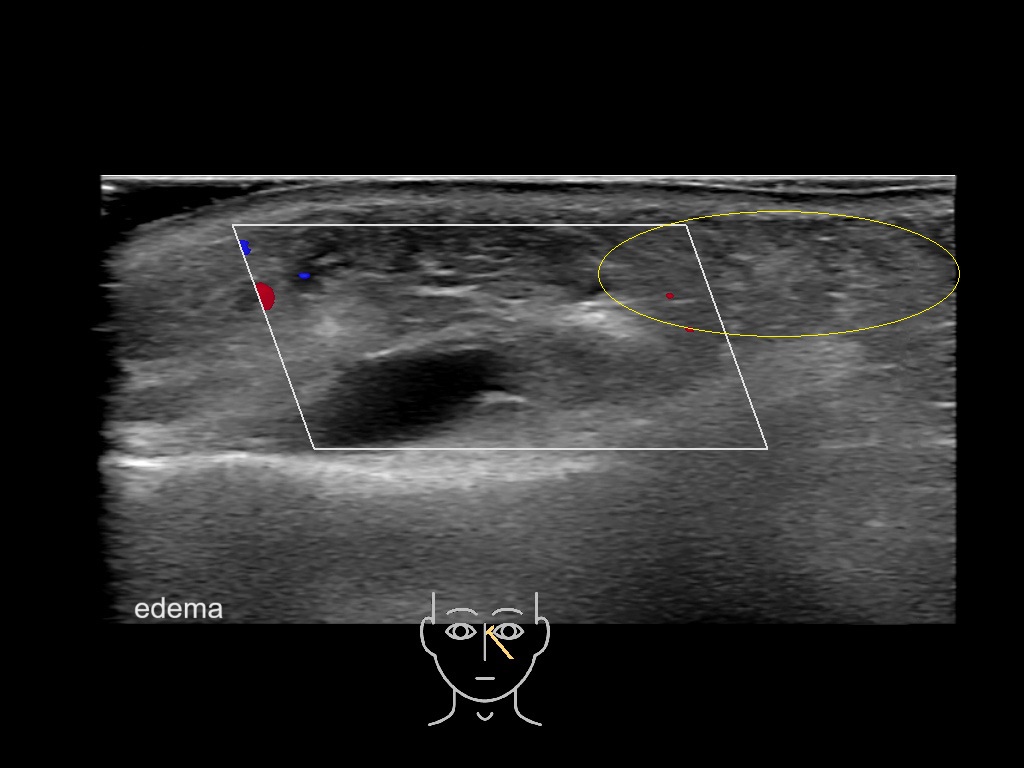

With ultrasound signs of inflammation can be visualized. Edema can be seen as a hyperechoic appearance of the subcutaneous fat, sometimes separated by hypoechoic fluid filled area’s, known as cobblestone appearance. Increased vascularization (hypervascularity) can be seen on colour Doppler. An abscess will appear as a fluid collection appearing as an irregular hypoechoic area with heterogeneous internal echoes and a thickened wall. Posterior acoustic enhancement can be present, and there is vascularity around but not within the mass. Under ultrasound guidance, abscesses can be managed by needle aspirations (18G) under antibiotic cover.

Study the first image to recognize the different layers. If you are sure about the layers, swipe to the second image to view the answer (if applicable).